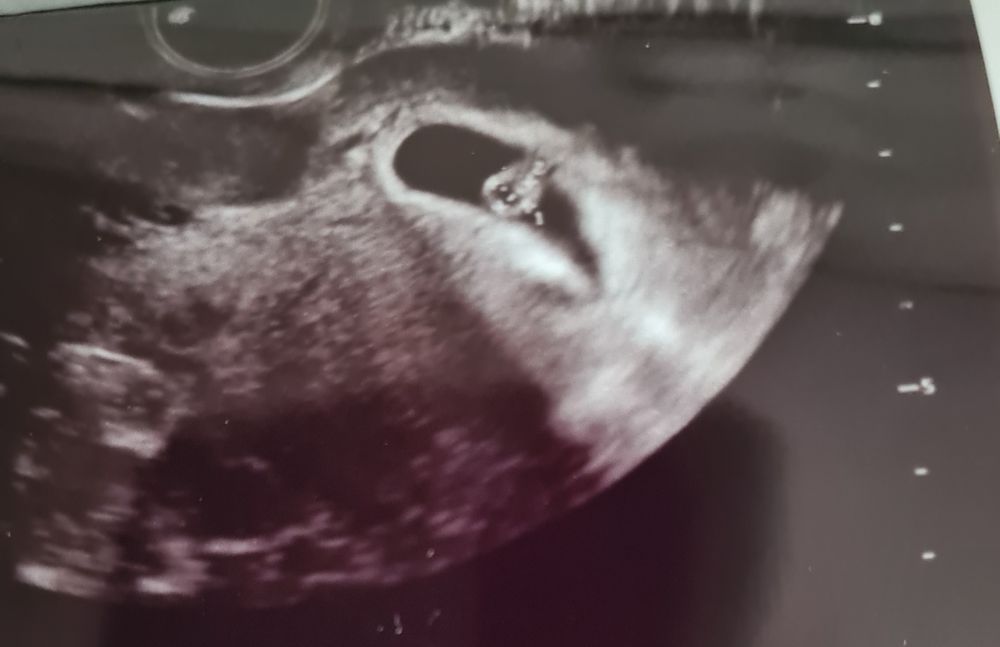

6 недель и 5 дней. Внеплановое узи.

Виктория Андрюшина, ох, а я в магазине была. Естественно не прокладок не сменной одежды не было. Муж с детьми бегал искал где прокладки купить, и рубашку что бы прикрыть огромное пятно на шортах( главное что не далеко от дома были. Сейчас гематома 13×19 мм. Сказали уже маленькая. Но перепугались мы все ужасно. Старший нас с узи встретил весь в слезах и с вопросом "все там больше нет малыша?" Очень обрадовался что все хорошо. Но не понял почему у меня так кровь шла.